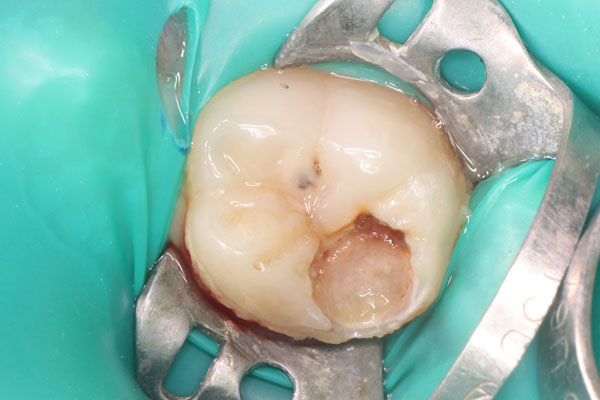

Лечение зубов

Лечение кариеса

-

Лечение кариеса (стоимость без учета снимка и анестезии)

12619

Лечение под микроскопом

-

Лечение кариеса под микроскопом (стоимость без учета снимка и анестезии)

14165

-

Эндодонтическое лечение пульпита под микроскопом ( за 1 канал) ( стоимость без учета снимка и анестезии )

24922

Лечение пульпита/периодонтита

-

Восстановление жевательного зуба после эндодонтического лечения

14320

Эндодонтическое лечение пульпита ( за 1 канал) (стоимость без учета снимка и анестезии)

22498

Примеры лечения зубов